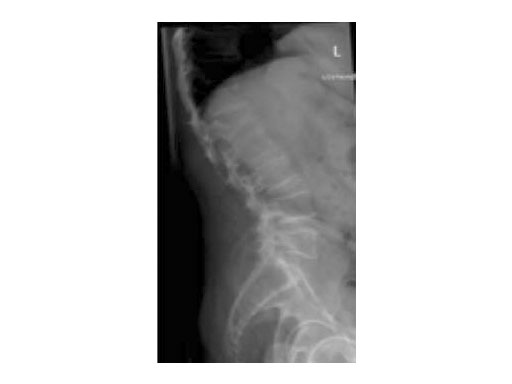

A 76-year-old man was affected by advanced osteoporosis (SD -2.5) (alcohol, steroids).